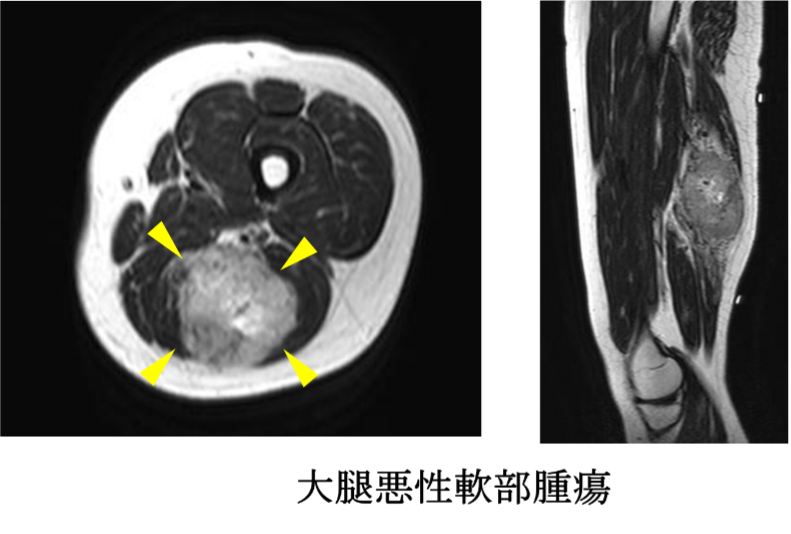

悪性腫瘍広範切除術

肉腫の手術は広範切除術が基本となります。肉腫は周囲の組織に目に見えない微小浸潤をしていることが多く、腫瘍だけを切除すると周囲から再発する確率が高いため、腫瘍を周囲の正常組織で覆って切除する“広範切除”が必要です。広範切除後の組織欠損に対して人工関節や骨移植、植皮、筋皮弁などを用いた再建が必要になることがあります。組織再建は皮膚科や形成外科と協力して行っております。